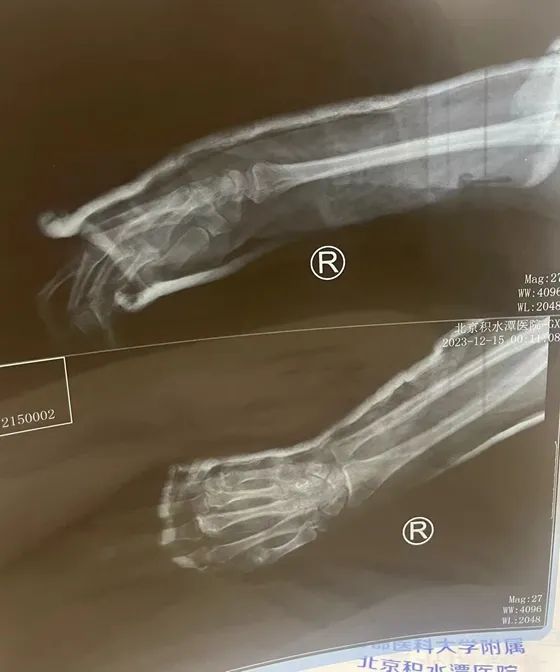

车到达北京站后,韩女士第一时间前往积水潭医院就诊,经过检查,得知骨折处对位比较好,有助于患处的恢复。

△韩女士在北京积水潭医院检查骨折位置